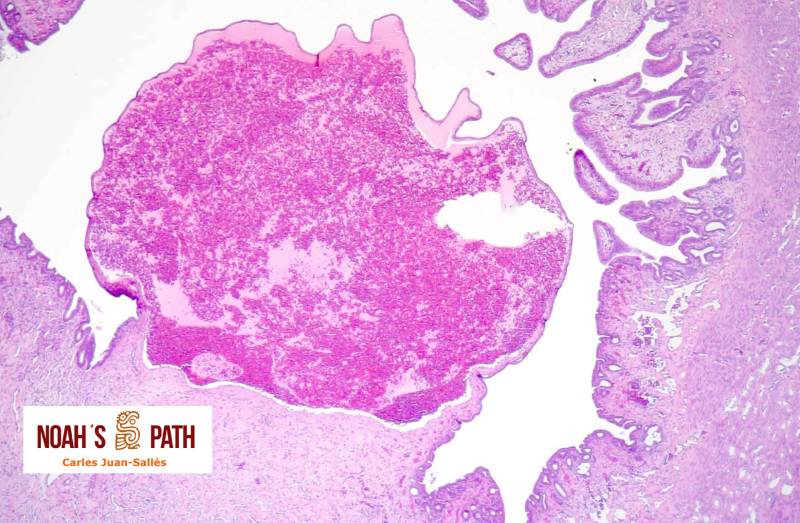

Adenocarcinoma tiroideo

Hurón